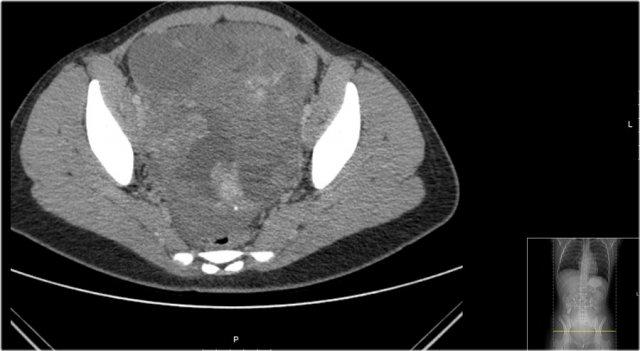

Đây là hình ảnh CT của một bé gái 13 tuổi biểu hiện với khối vùng bụng dưới.

Đây là một khối u vừa có thành phần nang vừa có thành phần đặc, kèm một số vôi hóa.

Các thành phần đặc không đồng nhất.

Khối u được phẫu thuật cắt bỏ và giải phẫu bệnh cho thấy u quái có thành phần ác tính, kèm di căn hạch bạch huyết.